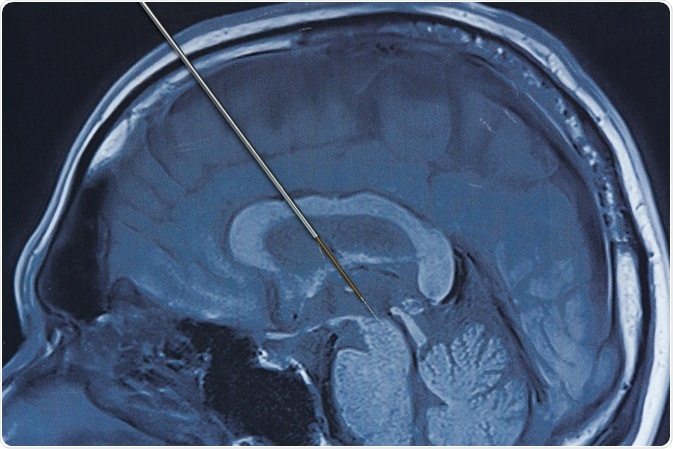

A local or general anesthetic is usually used while implanting the leads into the brain. A small hole is drilled into the skull, and the electrode lead is inserted stereotactically into the intended area of the brain. If the symptoms are primarily evident on the left side of the body, the lead will be placed on the corresponding right side of the brain and vice versa.

Prior to the procedure, imaging techniques such as magnetic resonance imaging (MRI) or computed tomography (CT) scanning is used to identify the problematic areas of the brain that will be targeting in the treatment. Some neurosurgeons opt to use microelectrode recording that monitors the nerve cells activity to identify the target areas.